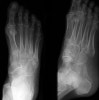

X-ray에서 발견하지 쉽지 않아 종종 놓치기도 합니다.

Oblique 45' view는 tuberosity fractures를 발견하기 유용합니다.

X-ray : 주상골 골절(Dorsal avulsion fracture)